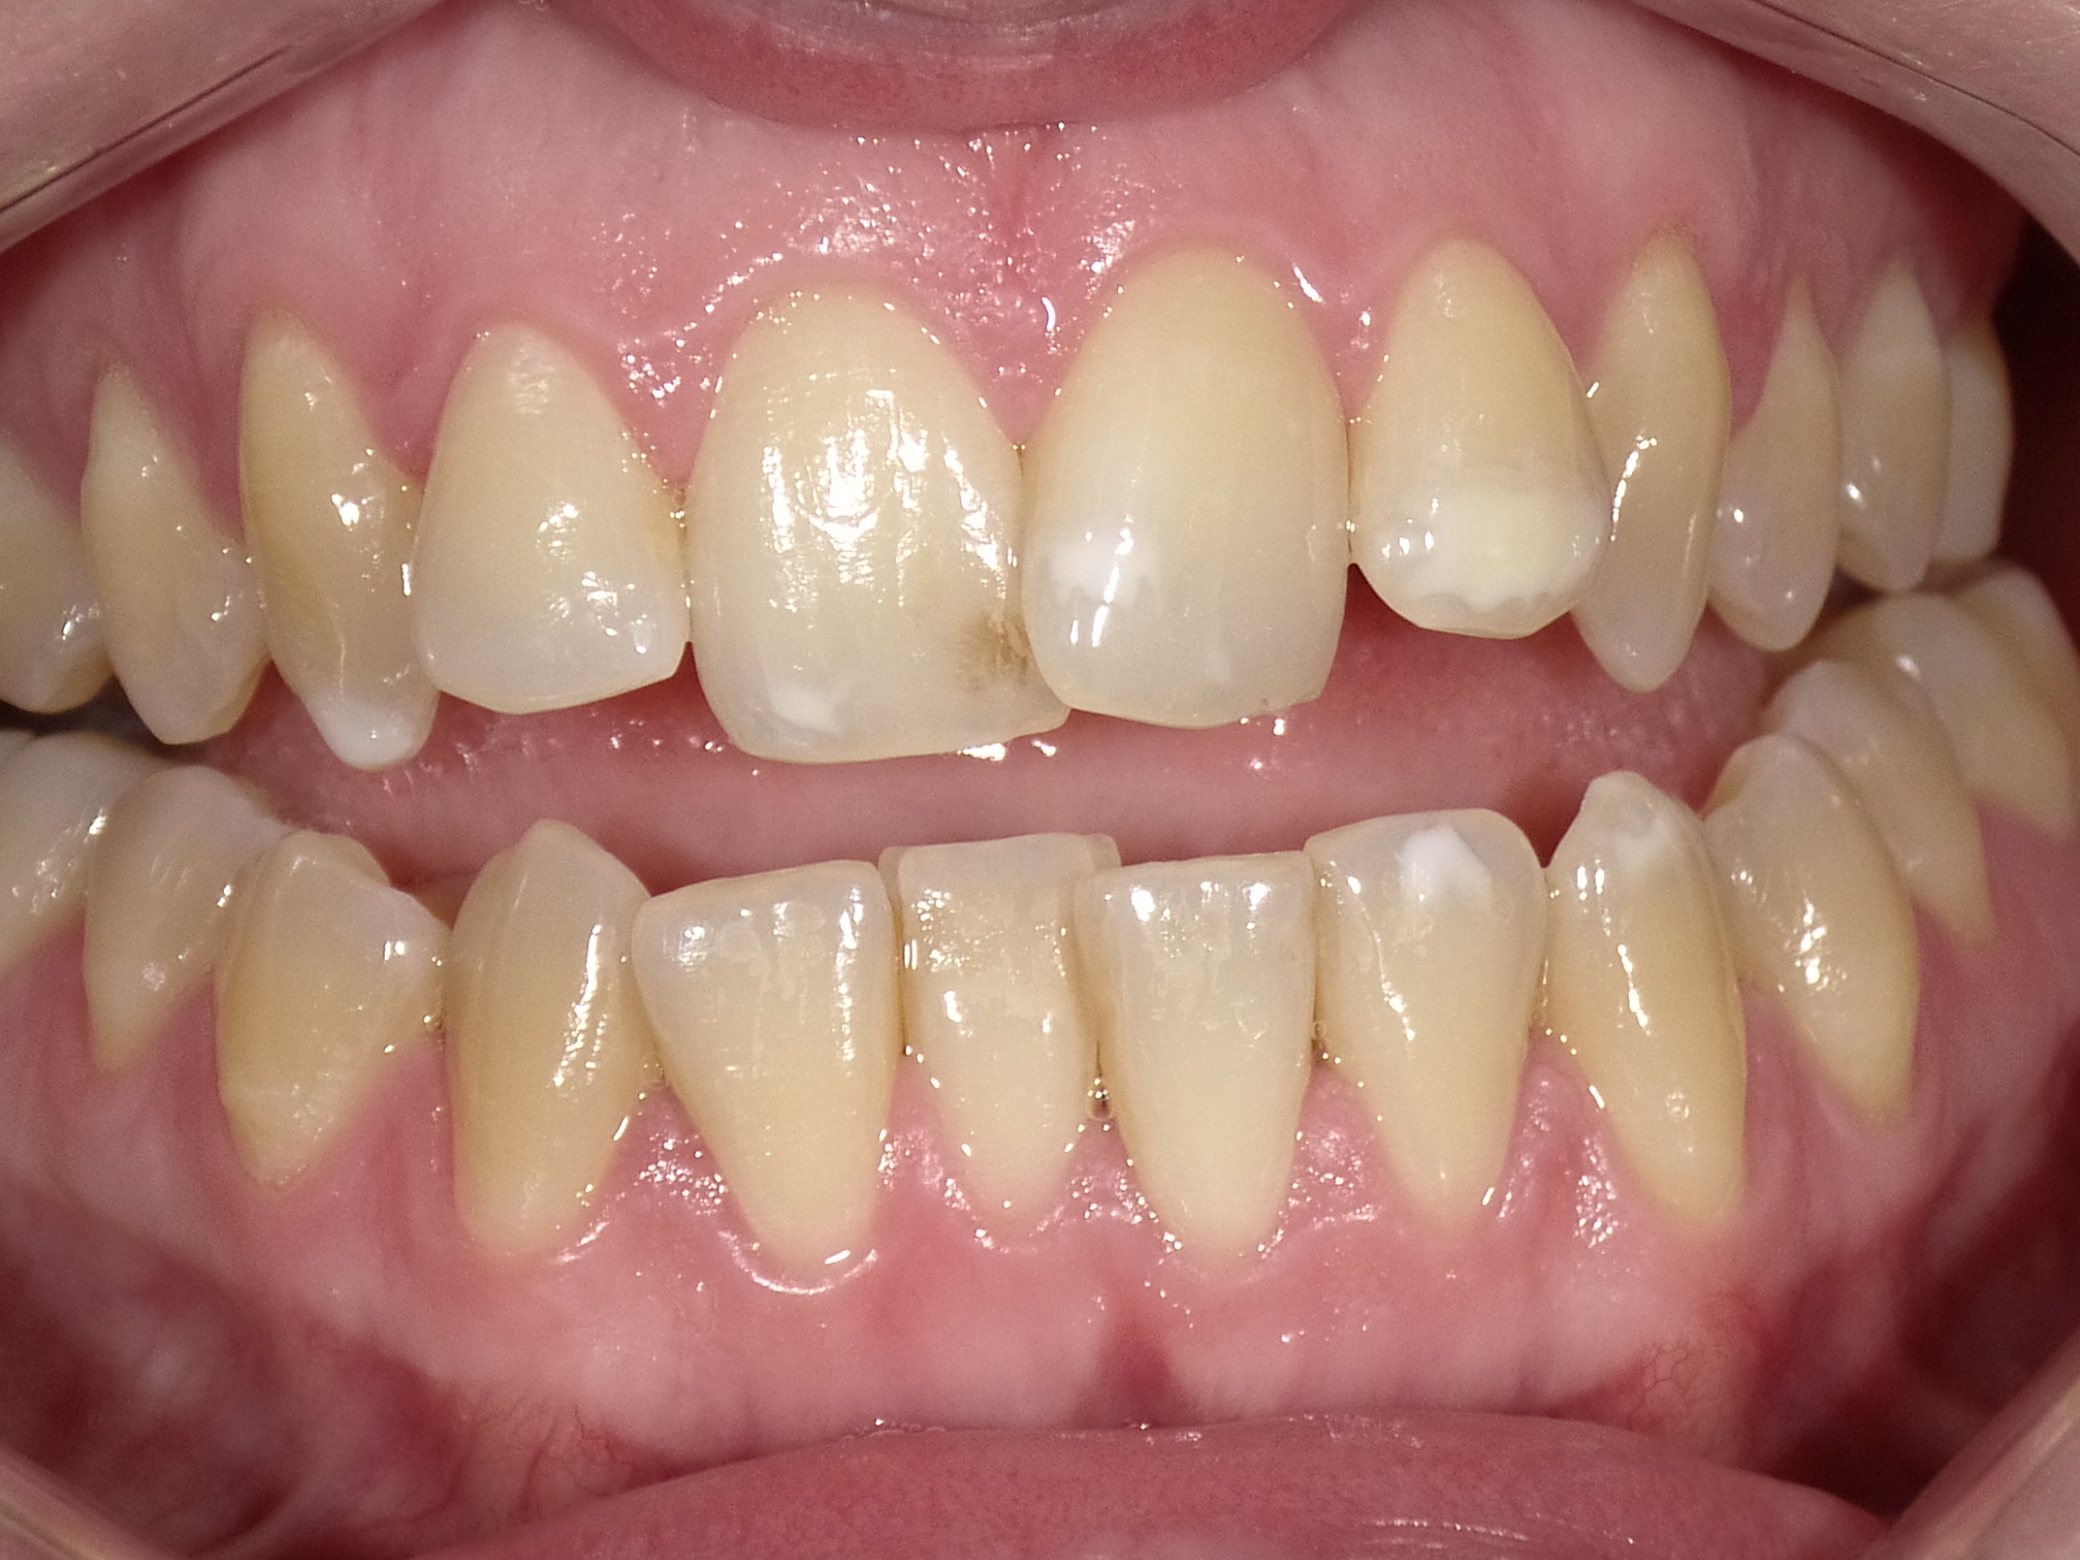

Teilweise Nichtanlage bleibender Zähne mit teilweise noch vorhandenen Milchzähnen, abgesunkener, lückiger Bisslage

Vorher: Teilweise Nichtanlage bleibender Zähne mit teilweise noch vorhandenen Milchzähnen, abgesunkener, lückiger Bisslage

Komplettbehandlung mit Bisshebung, Setzen von Implantaten als Ersatz für die Milchzähne, Schaffen einer völlig neuen, ästhetischen Gesamtsituation mit vollkeramischen Kronen und Brücken

Nachher: Komplettbehandlung mit Bisshebung, Setzen von Implantaten als Ersatz für die Milchzähne, Schaffen einer völlig neuen, ästhetischen Gesamtsituation mit vollkeramischen Kronen und Brücken